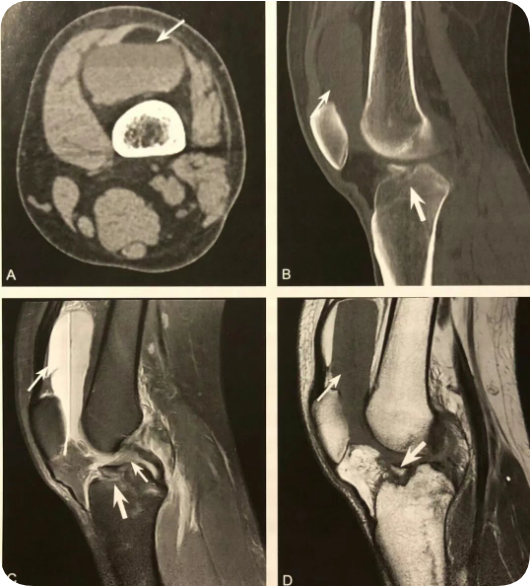

1. 腓骨小头撕脱性骨折的直接征象,弓形复合体和后外侧角损伤的间接征象;

2. 在膝关节X线前后位或 CT、MRI 冠状位观察,表现为近端腓骨小头或腓骨茎突撕脱性骨折,碎骨片呈弓形;

3. X 线片或 CT 观察到弓形征后,须行 MRI 检查,观察弓形复合体及后外侧角的完整性;

4. 少数后外侧角损伤合并腓总神经及胭动静脉损伤。